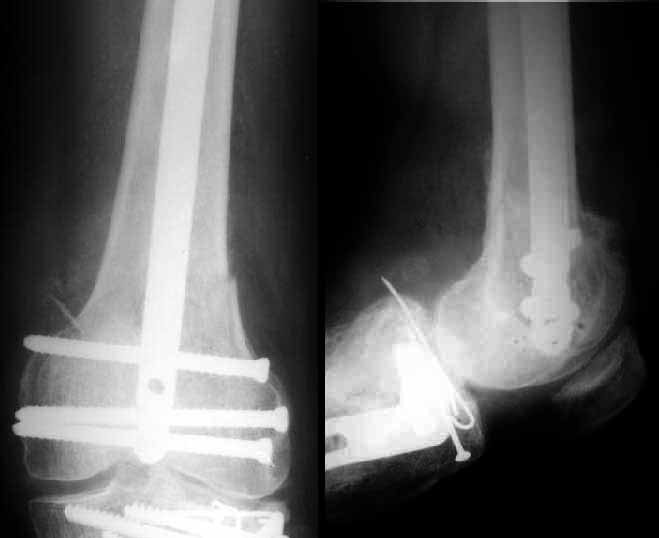

VMI> I was thinking of a retrograde nail because I thought the fracture was too low. I would love to see the postop Xrays.

Sorry but I've just prepared postop images - attached. A solid 13 mm nail was used. A few degrees of recurvation appears to be which i missed on image intensifier.

I'm still uncertain about advantages/disadvantages of ante/retrograde nailing for such fractures.

the postop radiographs look excellent. What do people think about driving an antegrade nail this distal as compared to retrograde nailing?